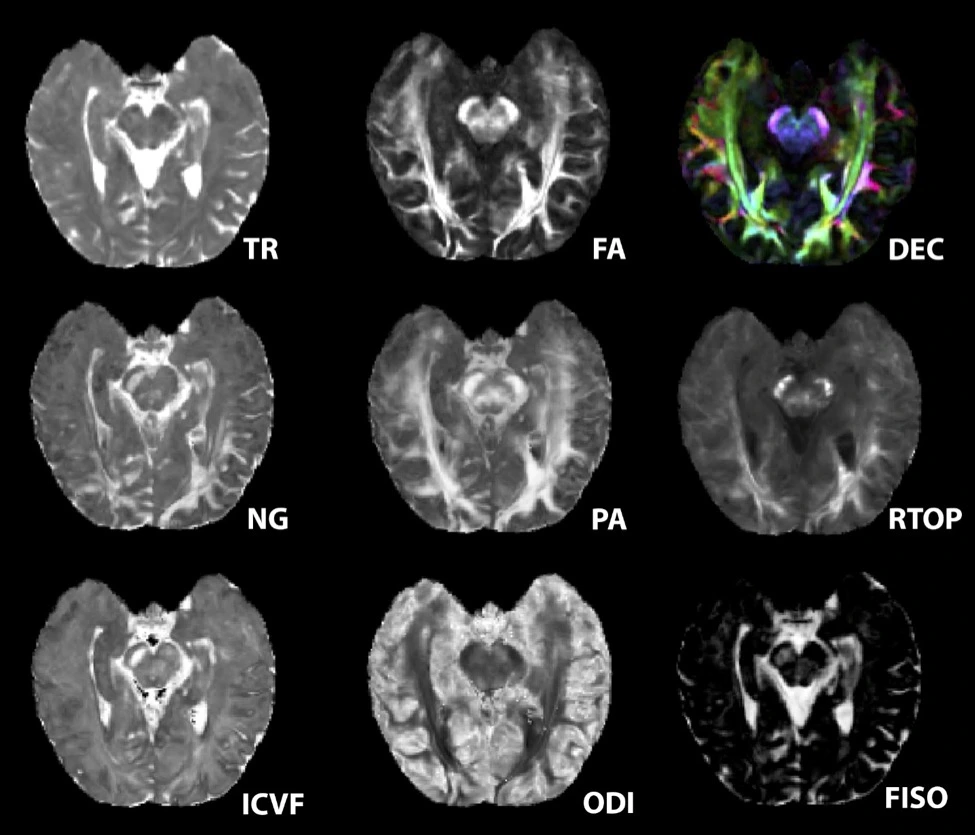

Microstructural MRI maps including diffusion, T2 and T1 methods to show different features in the healthy post-mortem human temporal lobe (Courtney Comrie)

Courtney Comrie